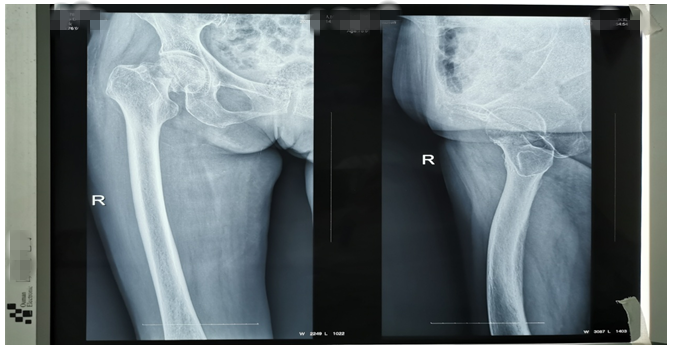

還有一位76歲鄧大媽,外傷致右側股骨頸骨折。外傷后因疫情鄧大媽一直未就診,在家非常痛苦,因疼痛不能平臥,一直坐位,臀部褥瘡形成,同時被骨折疼痛折磨地夜不能睡、不思飲食。鄧大媽基礎病較多,有高血壓病、腦梗塞、心臟病等病史,因骨折后時間長、錯位明顯,入院后積極治療內科疾病,完善各項輔助檢查,在麻醉師及內科醫(yī)師協(xié)助下,為鄧大媽成功行右側髖置換術,手術順利。術后鄧大媽的臉上又有了笑容,夜間也能休息好了,術后第二天就開始下床活動,家屬看到自己的老母親恢復地這么好,非常滿意。(見下圖)

右髖正側位手術前后對比圖